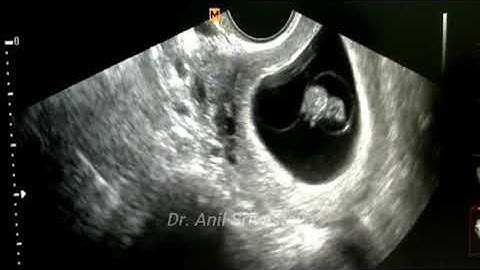

triplets triamniotic trichorionic pregnancy